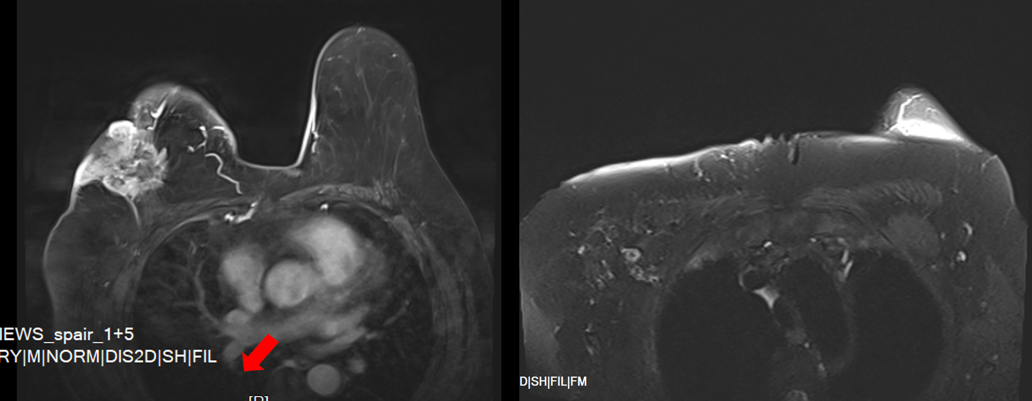

(2025-5-5)乳腺及腋窝淋巴结(双侧)MRI检查:1.右乳外上肿块4.6x5.1×3.9cm,MRI-BI-RADS V类。2.右腋窝淋巴结肿大:考虑癌转移(1.7×1.5cm)。